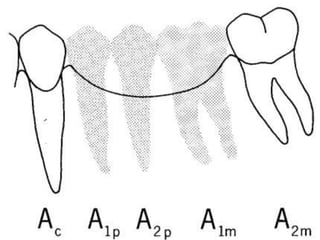

EVALUACIÓN DE PILARESProporción corona-raizConfiguración de la raízZona del Ligamento Periodontal (Ley de Ante)

Tylman: afirmó que dos dientes pilares son capaces de soportar dos póntIcos.Johnston y col.: LEY DE ANTELa superficie radicular de los dientes pilares, con soporte óseo periodontal, debe ser mayor o igual a la de los dientes a sustituir con pónticos